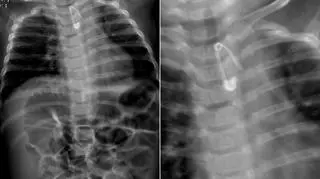

Rodzice Kuby przeżyli chwile grozy pod koniec września 2018 roku. To wtedy ich sześciomiesięczny wówczas synek połknął agrafkę. Przerażeni rodzice zawieźli dziecko do najbliższej placówki, czyli na SOR w Krotoszynie. Dyżurująca lekarka zleciła szereg badań. RTG potwierdziło: metalowy przedmiot tkwi w przełyku. W placówce nie było odpowiedniego sprzętu, by usunąć agrafkę. Dlatego dziecko skierowano do szpitala specjalistycznego w Ostrowie Wielkopolskim.

Dziecko połknęło agrafkę